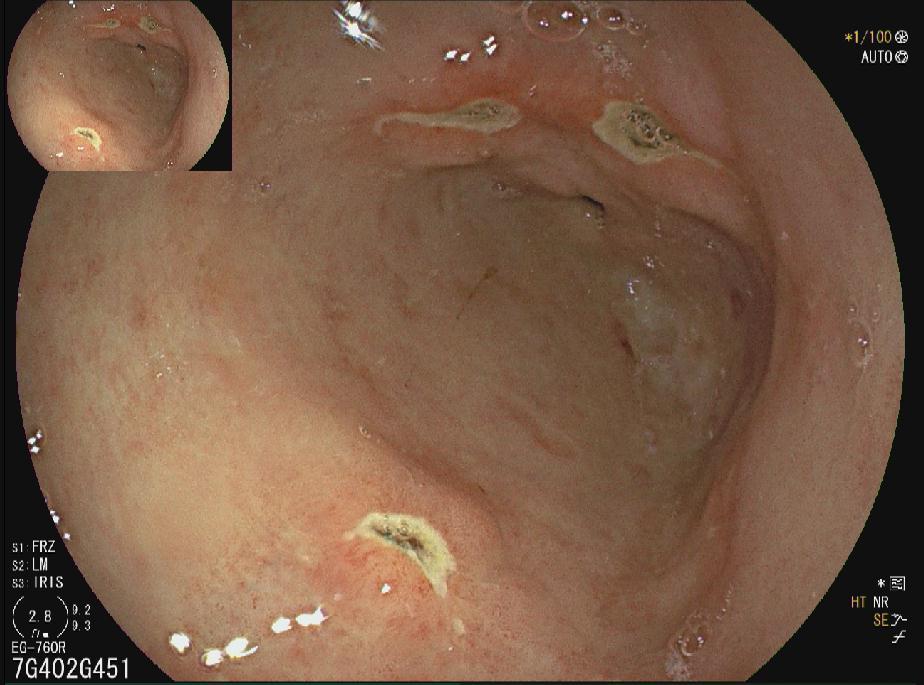

十二指肠球部溃疡

胃窦多发溃疡

胃窦溃疡

胃角溃疡

HPA感染鸡皮样胃炎

胃癌